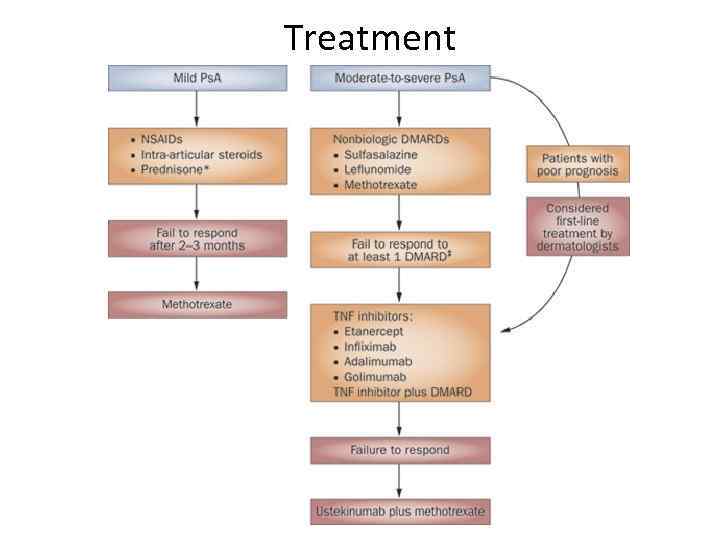

Treatment